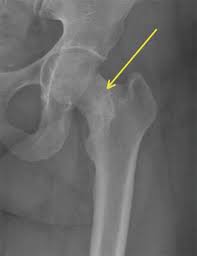

If an x-ray or MRI at the sports clinic confirms that youre experiencing a stress fracture in the hip the doctor will likely instruct you to rest. There are different operations which are. This depends on the fracture site and whether it is a simple crack or a displaced fracture.

Medications for Stress Fractures You can take over-the-counter medications to manage pain. Initial treatment of a hip stress fracture may include X-rays a magnetic resonance imaging MRI scan or a bone scan to further evaluate your condition.

How long does it take for a femoral stress fracture to heal. Medications for Stress Fractures You can take over-the-counter medications to manage pain. Heat treatments to alleviate pain and stiffness. Stress fractures under the femoral neck are less likely to be displaced and therefore they are usually treated by nonsurgical procedures. Treatment of Stress Fractures of the hip include. Initial treatment of a hip stress fracture may include X-rays a magnetic resonance imaging MRI scan or a bone scan to further evaluate your condition. This depends on the fracture site and whether it is a simple crack or a displaced fracture. Stress fractures which are tiny hairline cracks in the bone may or may not require surgery. Mobilisation exercises to maintain range of movement and flexibility.